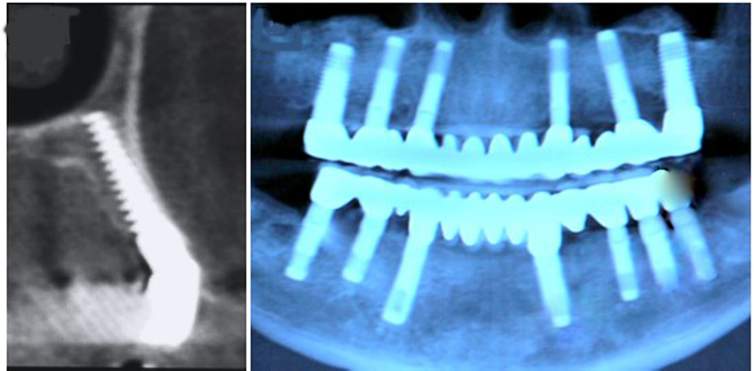

These are placed into facial bones that lie behind the upper jaw. They are long and angled so that they enter the mouth for restoration on either removable dentures or fixed bridges. The surgery is more complicated compared with conventional dental implant placement and not all surgeons can provide it.

In an external sinus lift, a small window is then opened in the bone. The lining of your sinus is gently pushed up and away from your jaw. Bone is packed in below the sinus. A membrane patch might be placed over the bone graft in the external approach. When the bone is in place the gum is closed with dissolvable stitches. The sinus lift is then allowed to mesh with your own bone, which can take 4-9 months, before placing dental implants. The amount of time depends on the amount of bone needed, and the graft material used.

In the internal approach your dentist will prepare the bone for implant placement and will gently tap up the bone under your sinus. Bone graft material will be packed into the space between the sinus lining and the jaw bone. This is done at the same time as implant placement where only around 3mm of extra bone height is required.